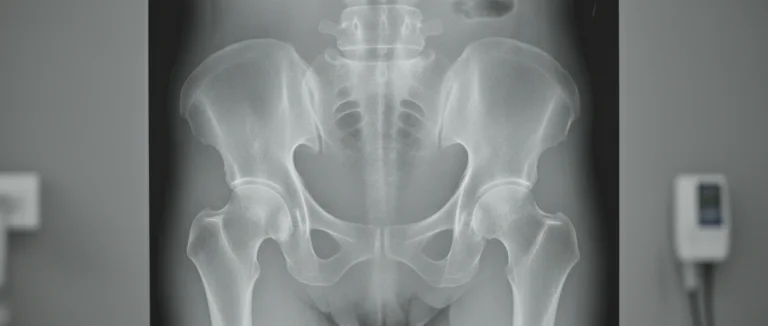

Точная диагностика является фундаментом эффективного лечения остеоартроза бедра. Врач‑ортопед обычно использует комбинацию клинического осмотра и инструментальных методов.

| Рентгенография | Сужение сустава, образование остеофитов, изменение плотности костей. |